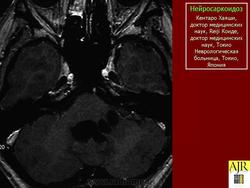

Грег А. Christoforidis, Эрик М. Spickler, Мария Владимировна Ресио и Бхарат М. Мехта

Рисунок 8

Рисунок 8 Нейросаркоидоз.